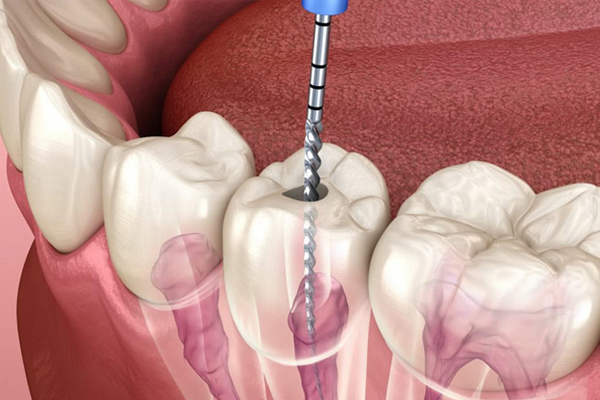

Our skilled dentists are commmited to provide precision dental care with compassion in creating radiant smiles. We are equipped with all the advanced and latest technology for every dental procedure. We follow top sterilisation protocols to make every dental experience the best. We also offer Full Mouth Scans – OPG enabling the patient understand his/her oral health better.

Our team includes Orthodontist Oral and Maxillofacial Surgeon, Implantologist, Prosthodontist, Endodontist, Kid’s Dentist, who follow strict standards to deliver exceptional care.